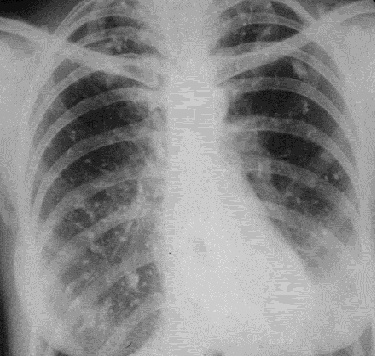

Различают два вида изменений внутренних органов при рентгенографии без применения контрастного вещества. Первый вариант - весь орган или отдельные его части становятся на рентгеноскопическом экране менее прозрачными и вроде затемненными (симптом затемнения), второй – наоборот, орган или отдельные части выглядят более прозрачными (симптом просветления). Рентгенограмма по отношению к изображению на рентгеноскопическом экране, является негативом. Поэтому светлым участкам на экране соответствуют темные на пленке (просветления, рис 2), и наоборот, темним участкам – светлые (тени, рис.3).

Рис. 2. Рентгенограмма органов грудной полости в прямой проекции. Слева на всем протяжении легочного поля – просветление.

Распространенное просветление встречается при пневмотораксе (рис 2). При этом, как правило, в медиальных отделах видим коллабированное легкое, смещение средостения в противоположный бок, а размещение газа не соответствует долевому строению легкого.